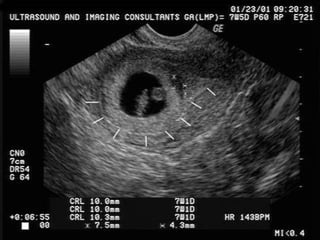

ultrasonographic diagnosis

 Definitive ultrasonographic diagnosis of an ectopic pregnancy is made in

only about 20% of cases, when an extrauterine pregnancy is clearly

identified (ie, an extrauterine gestational sac with a yolk sac or fetal pole is

visualized).